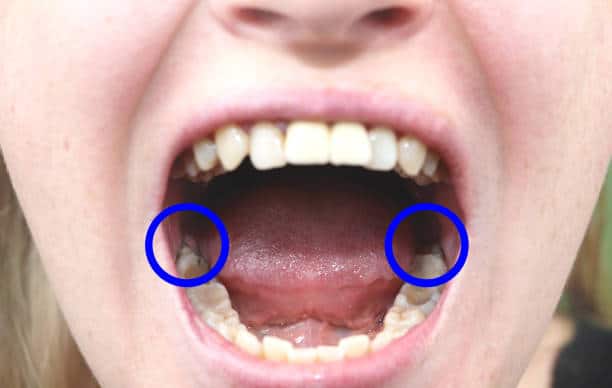

Why Are Wisdom Teeth Removed?

- Pain and Discomfort : Impacted wisdom teeth can cause severe pain and swelling

- Infections : Partial eruption can lead to bacterial infections, resulting in gum disease or abscesses.

- Crowding and Misalignment :Wisdom teeth can push other teeth out of alignment.

- Cyst Formation :In some cases, impacted teeth may develop cysts, damaging surrounding bone and teeth.

Wisdom Tooth Removal in Madinaguda

- Wisdom teeth, also known as third molars, are the last set of molars to emerge, typically in the late teens or early twenties. While these teeth can sometimes align properly, they often cause issues such as pain, crowding, or infection, necessitating removal.